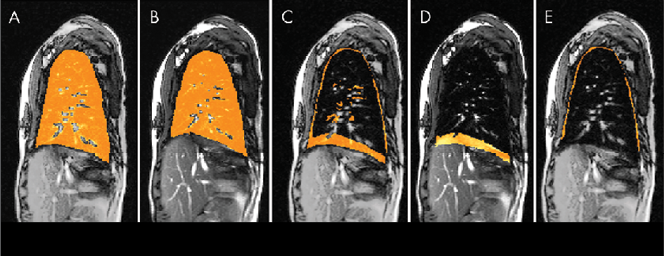

- Four-dimensional image construction was performed by obtaining a subset of the two-dimensional free-breathing dynamic MRI sections, which represents one four-dimensional volume over one respiratory cycle.

- The left and right lungs were then separately segmented in the four-dimensional volume at end inspiration and end expiration.

- By subtracting end-expiration images from end-inspiration images for each lung, lung excursion difference images are created, from which the chest wall and diaphragmatic components of lung excursion are derived separately.